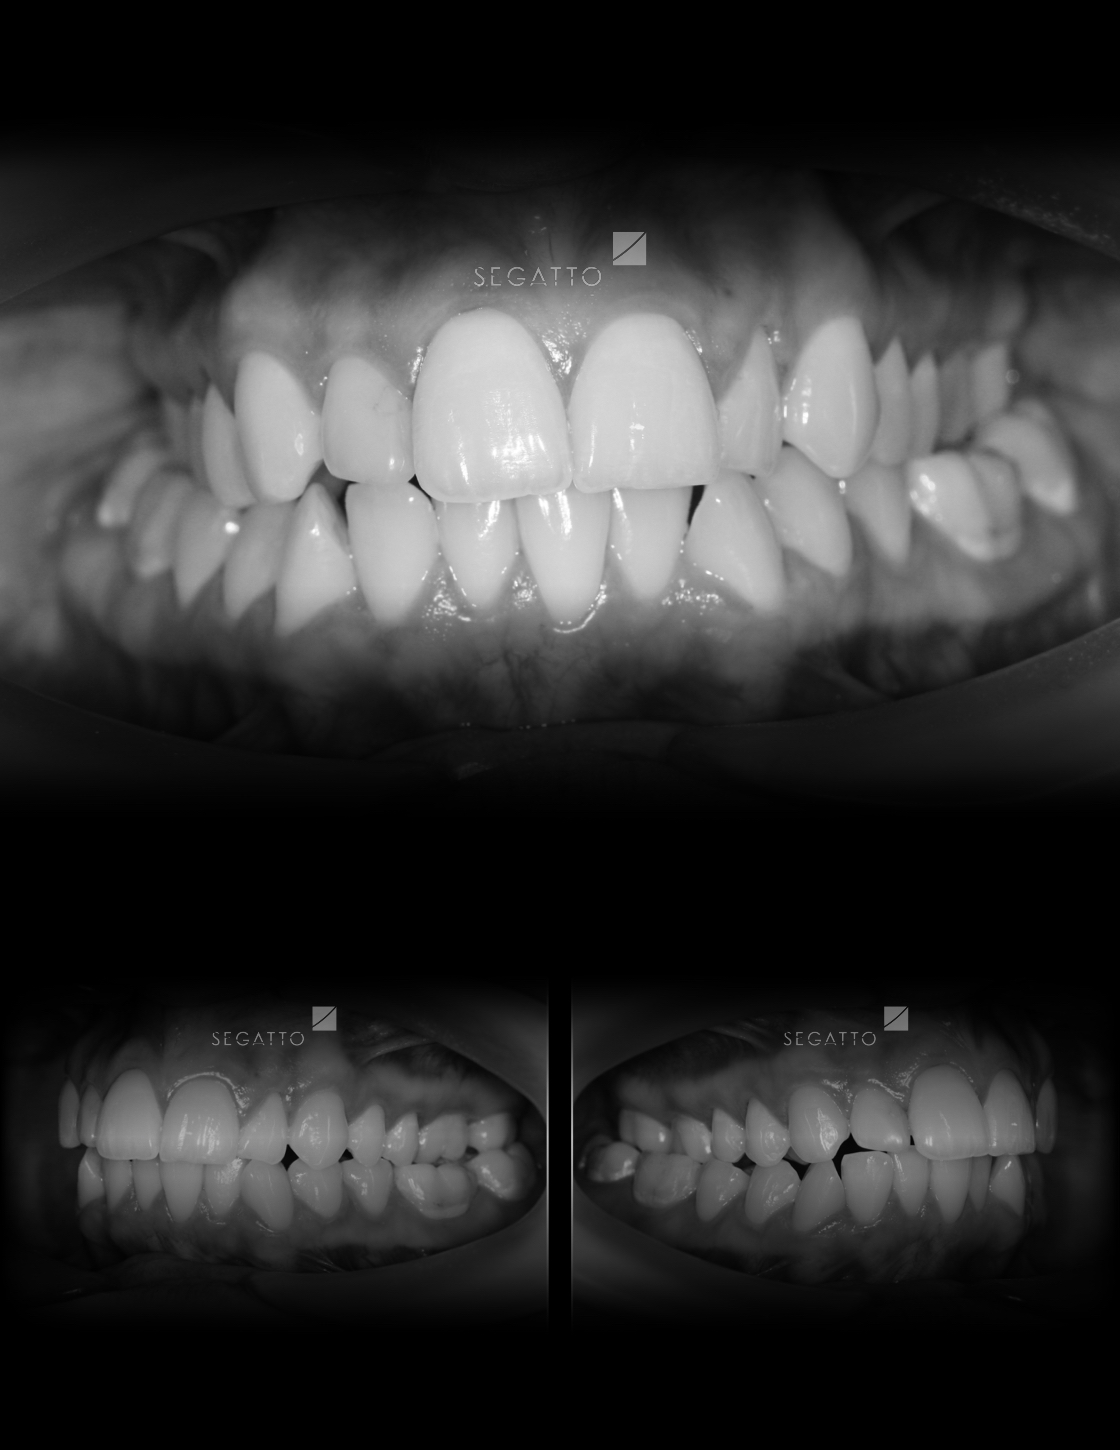

Orthodontics

Cases